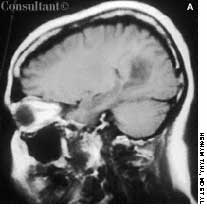

A 47-year-old man presented to theemergency department with adrooping right eye. He also complainedof a constant right-sidedheadache of 1 week’s duration; thepain involved the temporal region.Another physician had diagnosednew-onset migraine and prescribedsumatriptan, which failed to alleviatethe pain. The patient had no weakness,vomiting, or double vision.Both his father and his son hadMarfan syndrome.